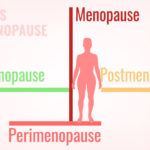

5 Treatment Modalities to Manage Menopause

Author –Dr Preety Aggarwal MBBS, DGO, DNB, Medical Director (Gurgaon)- Obstetrics and Gynaecology 5 Treatment Modalities to Manage Menopause Introduction: Menopause refers to the cessation of periods or menses. It is a natural process of ageing caused by the depletion of ovarian reserves as well as the fall of hormones including oestrogen and progesterone. According […]

Menopause and Urinary Symptoms

Menopause and Urinary Symptoms Menopause and Urinary Symptoms Author: Dr. Tejinder Kaur MBBS, Diploma in Hospital Administration, Diploma of National Board training, Fellowship in Reproductive Medicine Consultant: Obstetrician & Gynaecologist at Motherhood Hospital, Mohali Menopause on average starts at the age of 51 in most women. This causes changes in the female body including urinary […]

How Menopause Affects A Woman’s Health?

Author: Dr. Manisha Tomar MBBS, DNB, DGOConsultant: Obstetrician & Gynaecologist at Motherhood Hospital Noida Approaching middle age often brings increased stress, anxiety, and fear. This can partially be attributed to physical changes, such as decreasing levels of estrogen and progesterone. Hot flashes, sweating, and other symptoms of menopause may cause disruptions. Menopause marks the end […]

Dealing With Menopause

Author: Dr. Teji Dawane, MBBS, MD (OBGYN)Consultant: Obstetrician & Gynecologist at Motherhood Hospital Whitefield Bangalore Menopause is a change into another stage of life. It starts when the menstrual cycle ends. Menopause isn’t a medical issue, and some experience it as a period of freedom. But hormonal changes and different components involved can cause inconvenience. […]